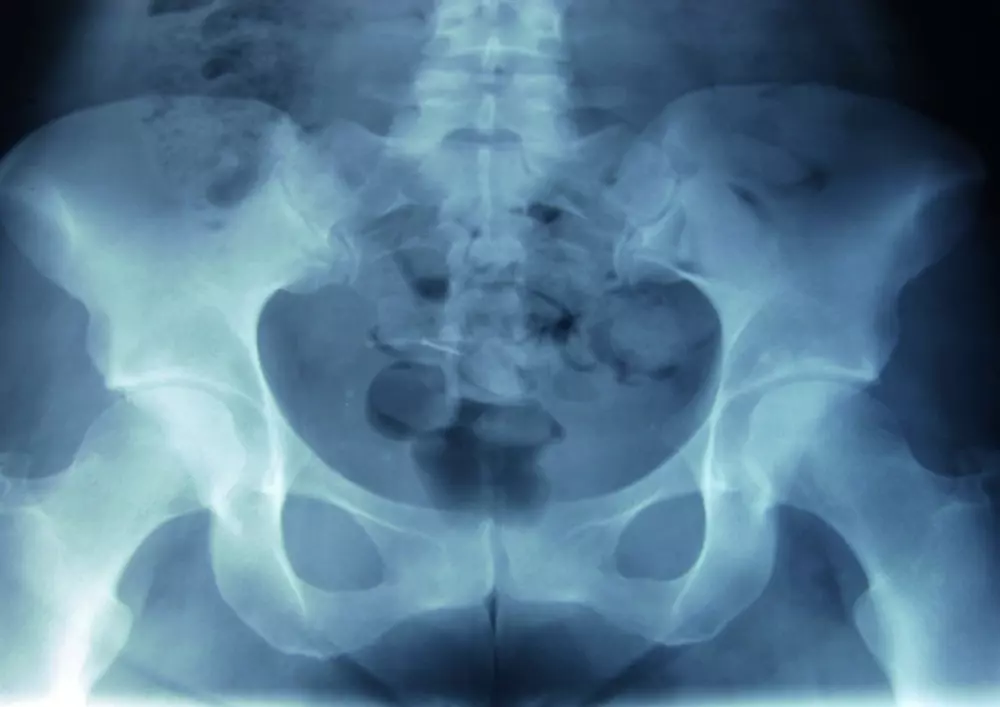

Metoda McKenziego w rwie kulszowej

W dziale „Z praktyki gabinetu” znajdą Państwo tekst pt. „Metoda McKenziego w rwie kulszowej. Opis przypadku”. Bóle kręgosłupa dotyczą bardzo dużej części społeczeństwa, co może mieć źródło w siedzącym trybie życia i ograniczeniu aktywności ruchowej. Choć lekarze i fizjoterapeuci nieustannie poszukują nowych metod walki z bólem, do najpopularniejszych wciąż należy właśnie metoda McKenziego. Krzysztof Czupryniak przedstawia przypadek 32-letniej kobiety, spędzającej większość czasu w pozycji siedzącej, jednak uprawiającej przy tym jogging 3 razy w tygodniu. Opisuje badanie przedmiotowe oraz poszczególne sesje fizjoterapii z wykorzystaniem wspomnianej metody.